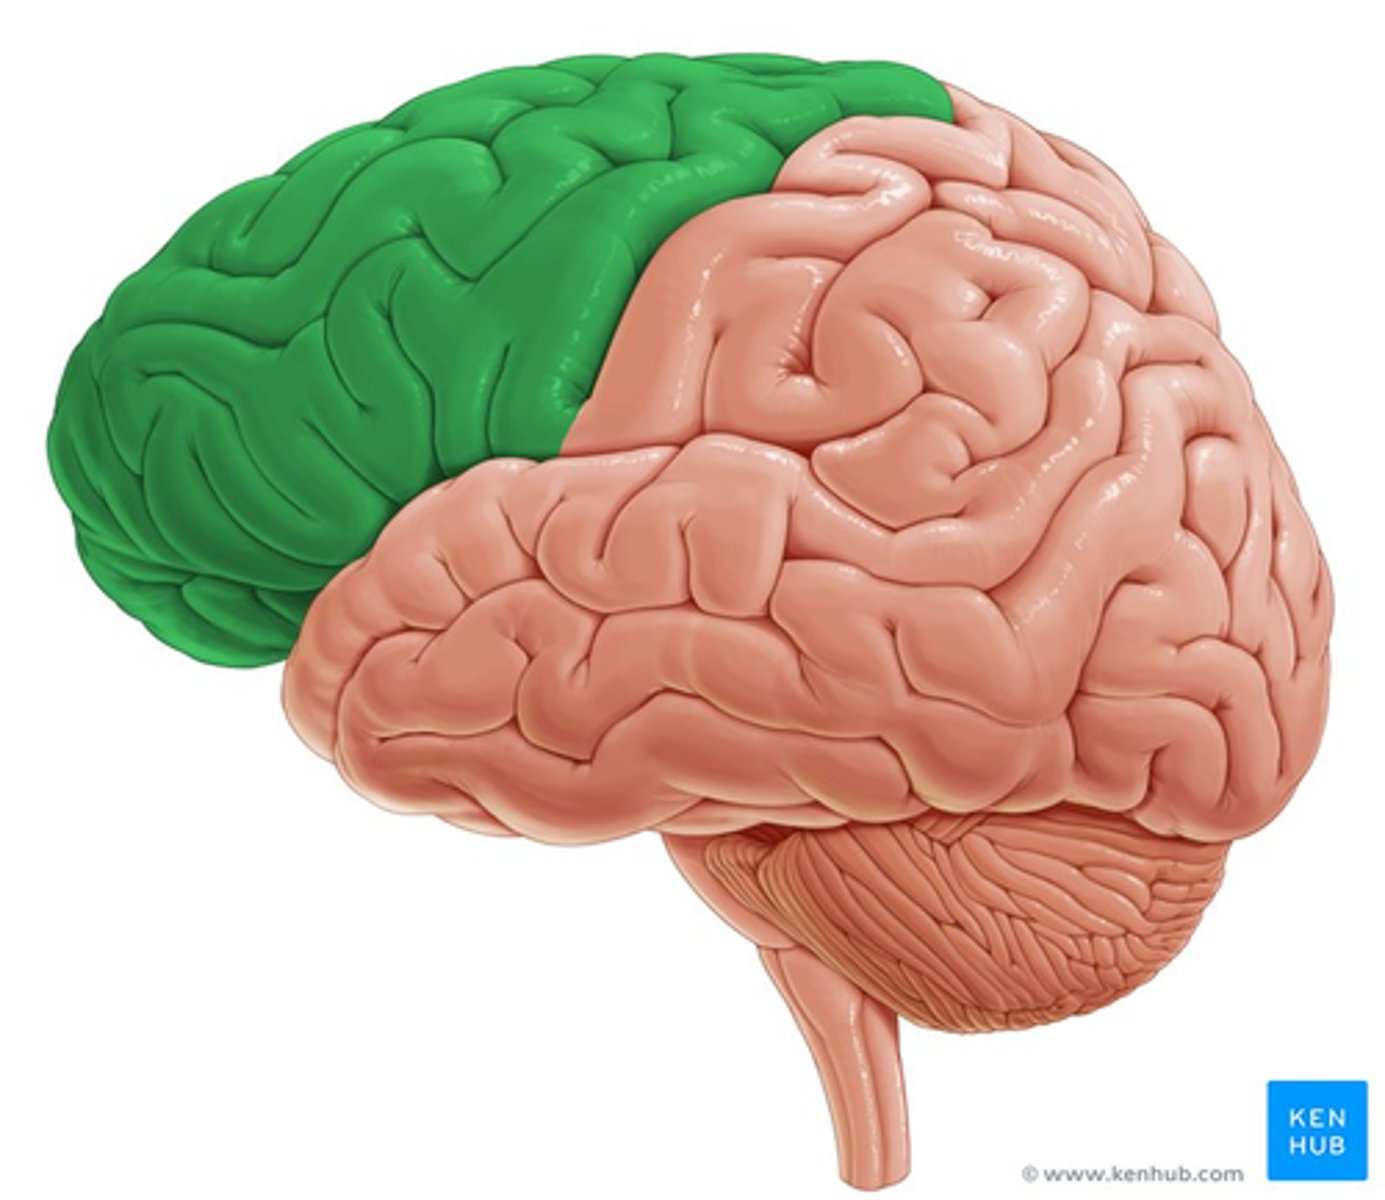

frontal lobe